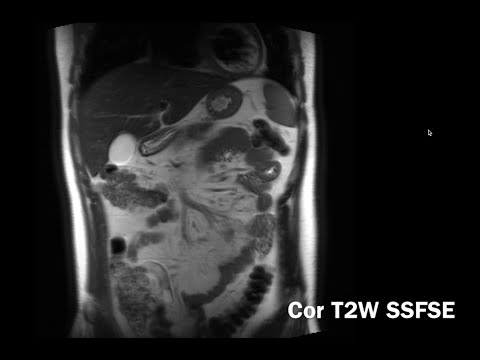

Textbooks can't teach you how to read a scan. This channel bridges the gap between theory and practice. I'm Rajesh, a radiologist in Toronto. I created this channel to give you the practical, real-world radiology training I wish I had as a resident. My videos are the antidote to the overwhelm from bloated textbooks and abstract lectures. They will help you: 1. Learn systematic, practical approaches to complex studies like CT and MRI. 2. Understand foundational concepts taught simply, from first principles. 3. Master the high-yield anatomy and pearls that matter in real-life practice. 4. Build the confidence to avoid simple mistakes and feel ready for your next shift. But watching videos isn't enough. You can only truly learn radiology through practice. That’s why we built the platform on NavigatingRadiology.com -- an interactive system with a full screen PACS viewer, curated high-yield courses, and an “AI Attending” that gives you instant feedback and guidance. Try it today!